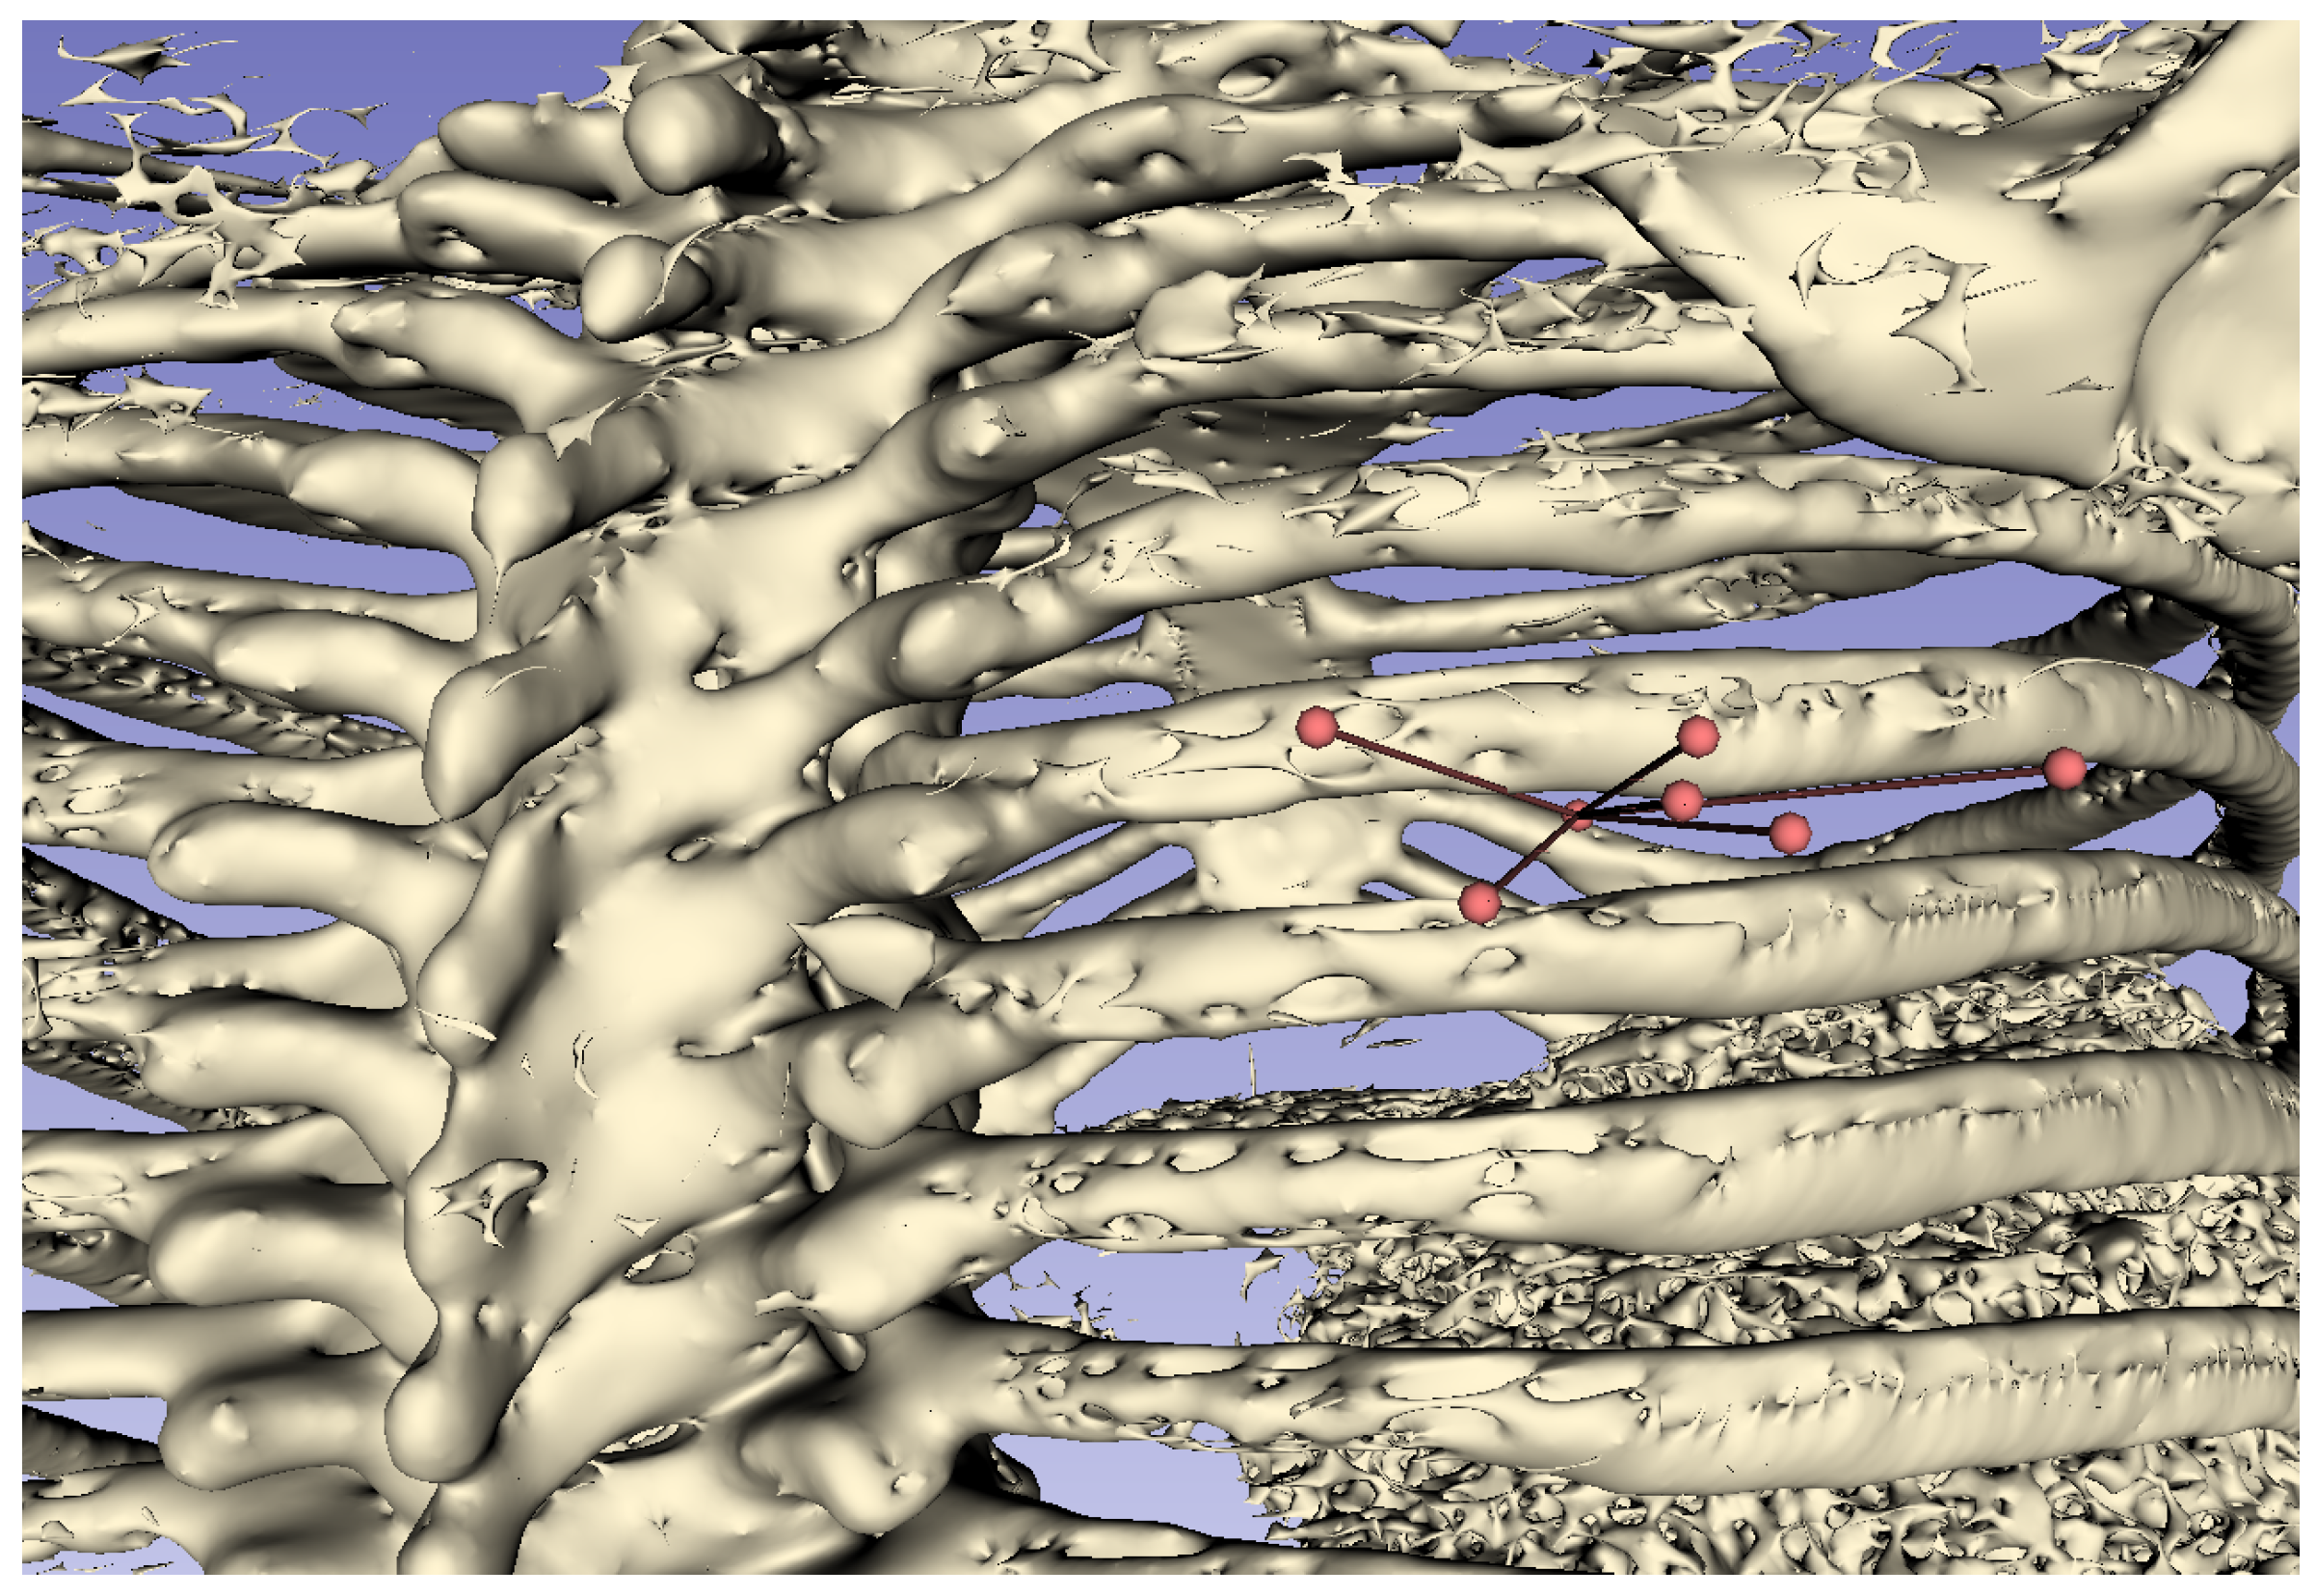

6.2. Processing Time to Derive Puncture

Figure 10 shows the puncture routes derived by the proposed method. The red spheres in the figure are the start and end points of the puncture, and the line connecting the two red spheres is the puncture route. In this evaluation, the human body was composed of 170 two-dimensional CT images, and these images were superimposed to create a three-dimensional CT image. The processing time required to derive the puncture route for a three-dimensional CT image using all 170 two-dimensional CT images was approximately 59.4 s.

For the puncture targets T 1 and T 2 , the visualization of the puncture routes are shown in Figure 11 and Figure 12, respectively. These figures show that all puncture routes pass through the bone, indicating that they are not puncturable routes.

Figure 10. Example of three-dimensional puncture route.

Jimaging 10 00251 g010